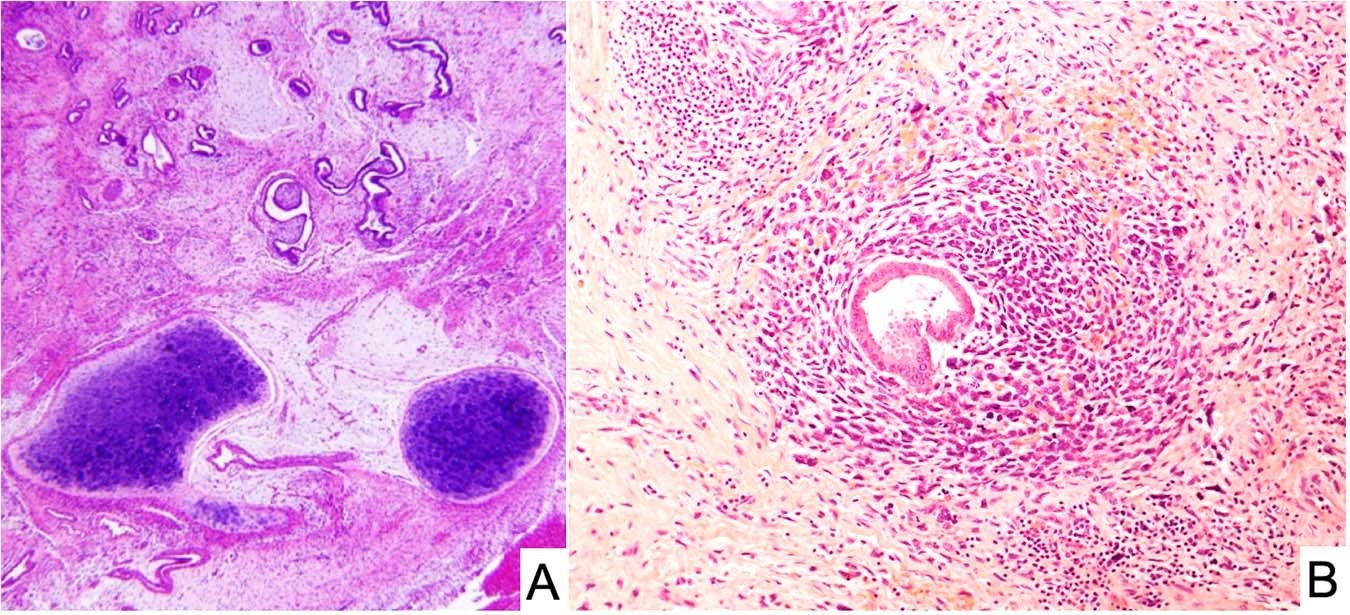

Fig. 9: Embryonal rhabdomyosarcoma of the cervix.

A A polypoid “vaginal” tumor presented in a 9-year-old female showing scattered endocervical glands with variably prominent subepithelial concentration of small cells and nodules of cartilage. PPB-type IR was also detected in the lung and a pathogenic heterozygous germline DICER1 mutation was detected. B Endocervical gland encircled by embryonal rhabdomyosarcoma in an 11-year-old female with a cervical-vaginal mass. She subsequently developed a Sertoli-Leydig cell tumor at age 13 years and had a pathogenic heterozygous germline DICER1 mutation.